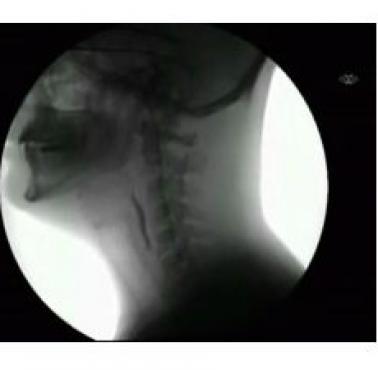

Żucie gumy i połykanie w promieniach rentgena (wideo)